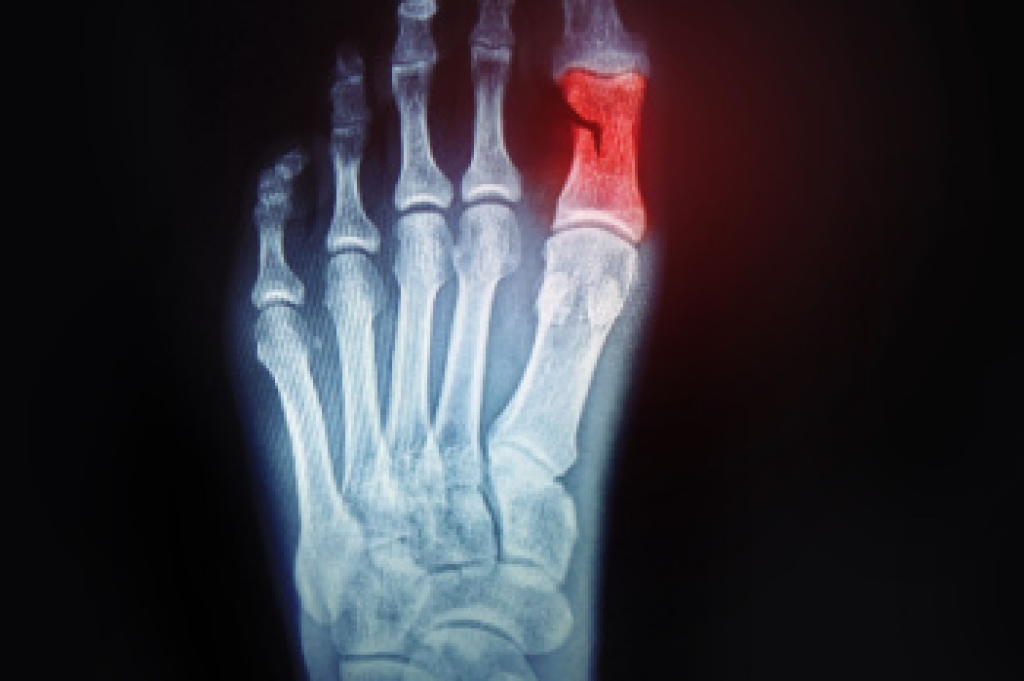

A toe fracture is a break or crack in one of the bones of the toe, typically caused by direct trauma or pressure. This injury often occurs due to stubbing the toe, dropping something heavy on it, or participating in activities that involve repetitive stress. The common signs of a toe fracture include pain, swelling, bruising, and difficulty moving or bearing weight on the affected toe. In some cases, the toe may appear misaligned or deformed. To diagnose a toe fracture, a podiatrist will perform a physical examination and may take X-rays to evaluate the extent of the damage. Managing the symptoms generally involves rest and elevation. Mild pain relievers can help alleviate discomfort. For more severe fractures, immobilization through splinting or buddy taping is often used. In rare cases, surgery may be necessary to realign the bones and ensure proper healing. If you have fractured your toe, it is suggested that you contact a podiatrist who can properly treat this condition.

Although most people try to avoid foot trauma such as banging, stubbing, or dropping heavy objects on their feet, the unfortunate fact is that it is a common occurrence. Given the fact that toes are positioned in front of the feet, they typically sustain the brunt of such trauma. When trauma occurs to a toe, the result can be a painful break (fracture).

Severe toe fractures may be treated with a splint, cast, and in some cases, minor surgery. Due to its position and the pressure it endures with daily activity, future complications can occur if the big toe is not properly treated.